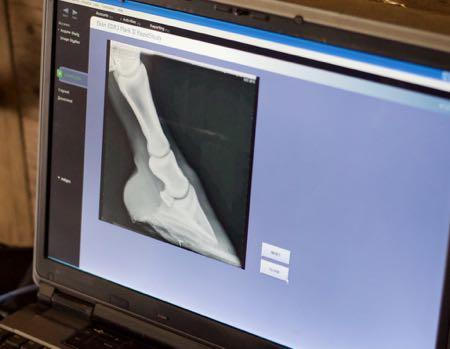

Treating Chronic Laminitis in Horses

Treating chronic laminitis in horses involves more than easing pain—it’s about long-term hoof health, dietary adjustments, and proactive prevention. By working closely with your veterinarian and farrier, you can manage inflammation, correct hoof balance, reduce triggers like excess pasture sugars, and monitor metabolic health to help your horse stay comfortable, mobile, and free from flare-ups.